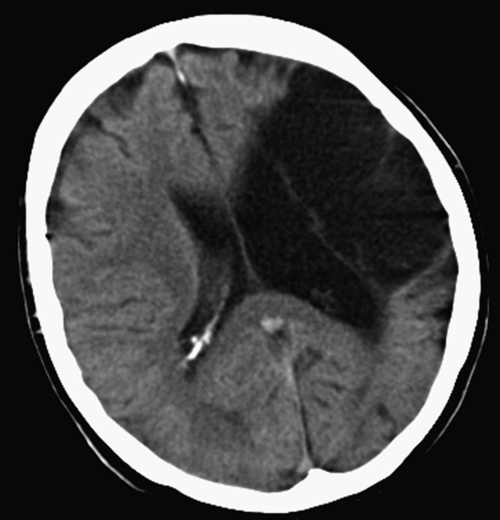

Stroke is a very common disease with a consistent persistent pattern of weakness and therefore the most common form of unilateral weakness that will appear in OSCEs. You should therefore know about common patterns of stroke so you can gain extra marks (Fig. 3.9.1). The Bamford classification subdivides stroke into the following clinical presentations:

You may be asked to comment on a CT or MR scan—this is similar to commenting on an X-ray (see station 7.2). Compare the sides and look for the obvious abnormality. Remember in stroke the infarct will be on the contralateral side to the clinical signs.